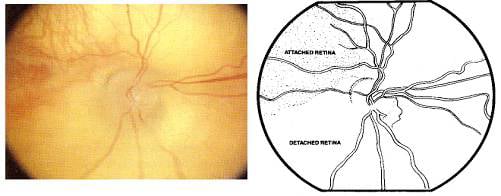

Página 296 - 9.2. Sistema visual

Página 323 - 9.3. Evolución de la ROP